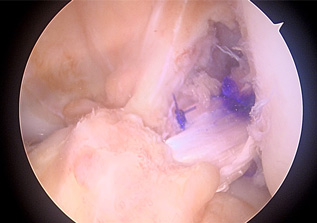

• 画像:断裂した十字靱帯(関節鏡)

断裂した十字靱帯(関節鏡)

関節鏡を駆使して、靭帯の再建術を行います。半月板損傷などの合併損傷が有る場合は、追加して処置を行います。

• 画像:再建した前十字靱帯(関節鏡)

再建した前十字靱帯(関節鏡)